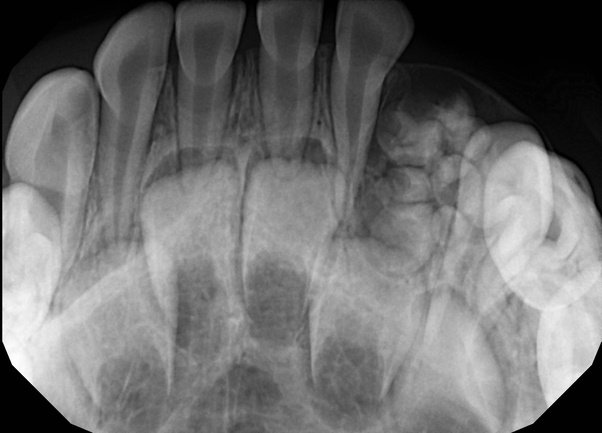

Выявить даже незначительные обломки можно с помощью рентгена. Срочный визит к стоматологу поможет избежать остеомиелита челюсти.

Если так случилось, что после извлечения корневой части, там осталась даже не значительная его часть, первым делом нужно сделать рентгеновский снимок.

На нем будет видно:

- размер;

- форма;

- и место проблемы.

- перед удалением изучить состояние корневой системы и ее целостность на рентгеновском снимке;